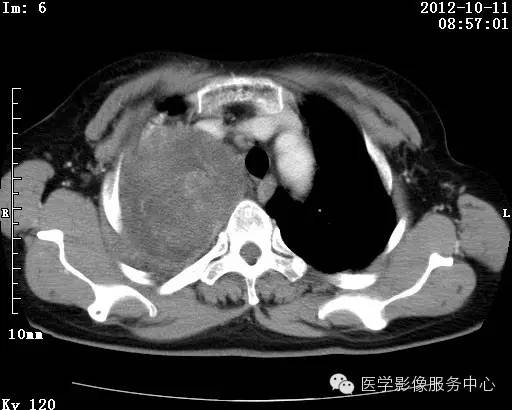

【病例】右肺巨大错构瘤1例CT影像表现

病史:女 65岁咳嗽咳痰 右肺巨大肿块就诊。

错构瘤的主要组织成分包括软骨、脂肪、平滑肌、腺体、上皮细胞,有时还有骨组织或钙化。错构瘤一般为实质致密的球形、卵圆形,也可以是分叶状或结节状,大多数直径在3cm以下。

错构瘤的发病年龄多数在40岁以上,男性多于女性。 绝大多数错构瘤(约80%以上)生长在肺的周边部,紧贴于肺的脏层胸膜之下,有时突出于肺表面。其特征钙化为爆米花样钙化,内有脂肪软骨成分等等。最常见的部位是胸膜下肺实质内,其次为主支气管或肺叶、肺段支气管内。

瘤内出现“爆米花样钙化”是诊断的主要指标之一。早期的点状、斑片状及结节状钙化 随时间增加钙化数量及范围会增加,最终可能演变 为爆米花样钙化;

另一项主要指标是瘤测得脂肪成分是诊断错构瘤。